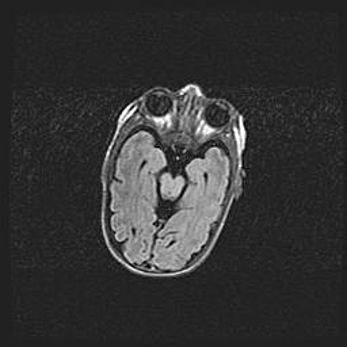

Сообщающаяся гидроцефалия. Кистозная энцефаломаляция головного мозга.

Возраст: 3 месяца 4 дня

Вес: 3100 г

Пол: женский

Окружность головы: 34 см

Срок гестации: 31 неделя

Кистозная энцефаломаляция головного мозга - одна из форм поражения головного мозга в детском возрасте. Характеризуется возникновением множественных и распространённых кист в коре, белом веществе и подкорковых образованиях головного мозга у плодов, новорождённых и детей раннего возраста. Развитие кистозной энцефаломаляции связано с внутриутробной асфиксией и гипотонией, родовой травмой, тромбозом синусов, пороками развития сосудов, инфекциями, сепсисом и другими причинами. Наиболее значимые инфекционные агенты: вирусы простого герпеса, цитомегалии, краснухи, токсоплазмы, энтеробактерии, золотистый стафилококк и другие.